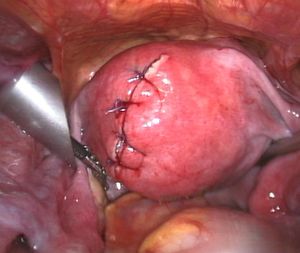

Myomectomy

Myomectomy is a surgery to remove one or more fibroids. It is usually recommended when more conservative treatment options fail for women who want fertility preserving surgery or who want to retain the uterus.[60]

- A laparoscopic myomectomy is done through a small incision near the navel. The physician uses a laparoscope and surgical instruments to remove the fibroids. Studies have suggested that laparoscopic myomectomy leads to lower morbidity rates and faster recovery than does laparotomic myomectomy.[61]

Laparoscopic myomectomy has less pain and shorter time in hospital than open surgery.[62]